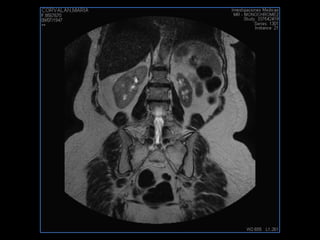

PROTOCOLO abdomen COR T2, AXIAL supresion grasa AX T1 +SAG T2  CON   GADOLINIO :  COR T1+AX T1(DIN) SAT: NO  FASE: RL THK: 6MM  COIL:  GAP: (FACTOR 1.4) 2MM FOV: 40 CM NEX:2 SINCRONIZACION RESPIRATORIA EN 3 O 4 CICLOS ALE

PROTOCOLO pancreas/ riñon AXIAL fat sat /AX in phase out phase AX T1 +SAG T2  COR T2, CON   GADOLINIO :  COR T1+AX T1(DIN) SAT: NO  FASE: RL THK: 4MM  COIL:  GAP: (FACTOR 1.4) 1MM FOV: 40 CM NEX:2 SINCRONIZACION RESPIRATORIA EN 3 O 4 CICLOS ALE

resonancia de abdomen